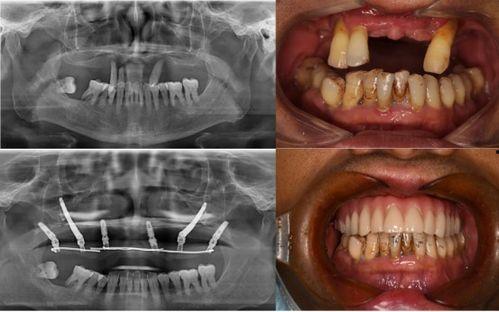

佛山种牙爆料事件最新情况,最新进展与各方回应梳理

最近佛山那边的种牙事件可是闹得沸沸扬扬的,咱们得好好来聊聊这个话题。你有没有听说,佛山某口腔医院因为种牙问题引发了一场不小的风波?别急,让我带你一探究竟,看看这背后到底隐藏着怎样的秘密。一、事件起因:患者反映种牙后问题不断话...